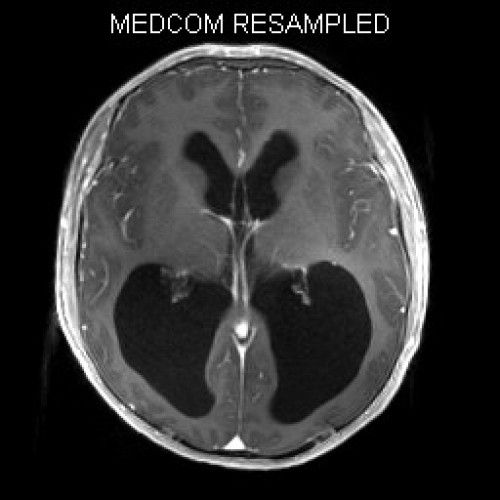

ICD: C75.3

ICD: G91.9

12-jähriger Junge. Die Eltern werden zu einem Gespräch bei der Klassenlehrerin gebeten, weil ihr Sohn sehr unaufmerksam geworden sei und seine Leistungen in der Schule bedenklich abgenommen hätten. Er droht das Klassenziel der 6. Klasse nicht zu erreichen.

Den Eltern war seit längerer Zeit bereits aufgefallen, dass sich ihr Sohn nach der Schule am liebsten ins Bett lege, um für eine Stunde einen Mittagsschlaf zu halten.